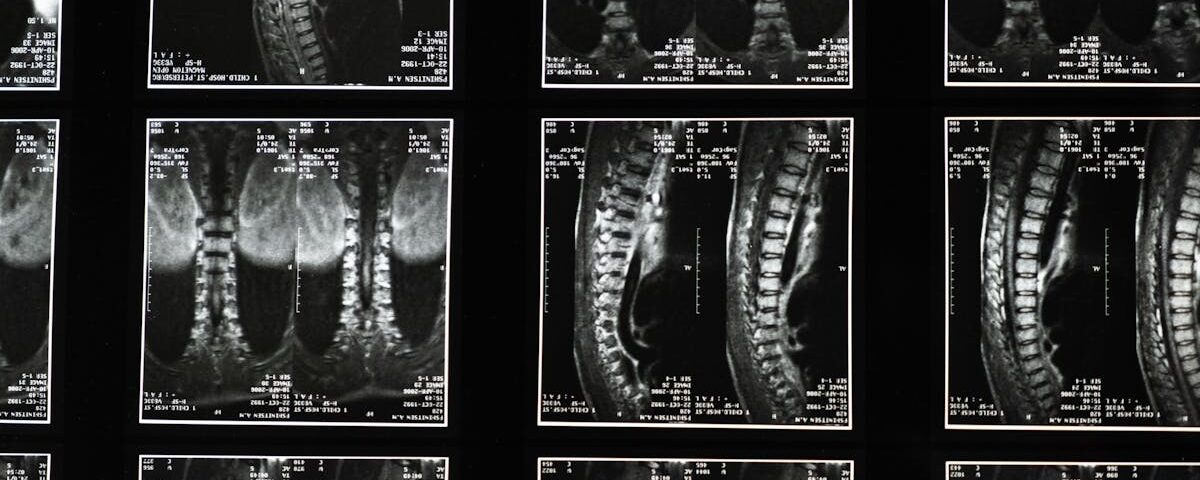

Quels examens permettent de diagnostiquer une hernie discale?

Une IRM ou une radiographie est utilisée pour confirmer le diagnostic d’une hernie discale.

Quels examens sont nécessaires avant de commencer un traitement de décompression?

Une IRM ou une radiographie est généralement nécessaire pour évaluer l’état de la colonne vertébrale.